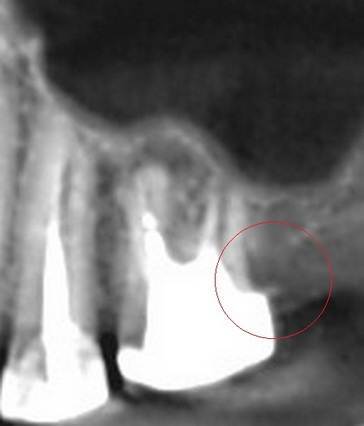

Александр В.В. Опубликовано 29 марта, 2023 Поделиться Опубликовано 29 марта, 2023 (изменено) Здравствуйте! Уже давно на шестом верхнем зубе есть гранулёма или киста размером 5-6 мм. Несколько лет назад пробовали класть кальций в каком-то виде, но, видимо, не помогло. Сейчас всё-таки решил перелечить этот канал, но эндодонтист сказал, что это только часть дела и надо делать все каналы. Кроме того, как я понял, проблема не в том канале, который запломбирован, а в том, который проходит рядом с ним и не был обнаружен и запломбирован. На этом снимке это верхний левый корень и в его правой части темное пятно - это вроде и есть тот ненайденный канал. Здесь видна гранулёма и запломбированный канал (корень слева). А здесь справа от запломбированного канала (левого корня), тот самый незапломбированный. Но у меня есть сомнения по поводу такого вывода, потому что в других каналах можно обнаружить более очевидные "темные каналы" в зависимости от среза. На этих снимках обращаю ваше внимание на правый канал. Если нужно, могу предоставить другие проекции, потому что имею диск с данными КЛКТ. Вопросы. 1. Действительно ли на снимке ненайденный канал на корне зуба с гранулёмой? 2. Возможно ли перелечивание одного канала с гранулёмой или кистой или нужно распломбировать сразу все каналы во всех корнях? 3. Если на снимке всё-таки ненайденный канал, то не кажется ли вам, что он прямой, а не изогнутый? Если прямой, его может обработать терапевт без использования микроскопа? Изменено 29 марта, 2023 пользователем Александр В.В. Ссылка на комментарий